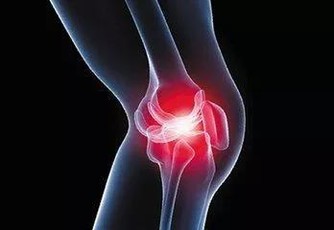

4、骨骼強壯。

中醫認為,腎主骨,骨靠腎精滋養,腎好骨才好。腎氣衰敗會出現骨質疏鬆、腰酸背痛,甚至牙齒出現鬆動。